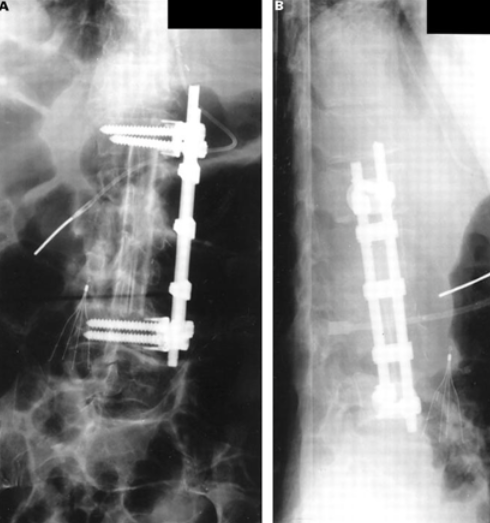

Anterior debridement, stru graft +/- poterior instrumentation

strut graft

Instrumentation